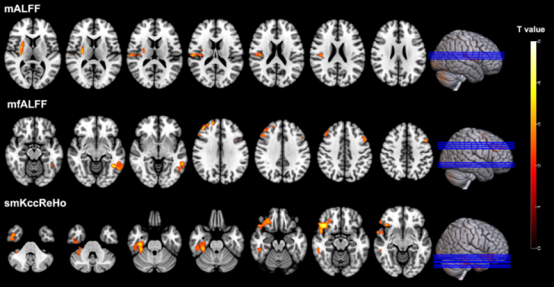

图2 SSc 患者与健康志愿者的脑功能低频振荡振幅(ALFF)和局部一致性(ReHo)差异(t 值分布)